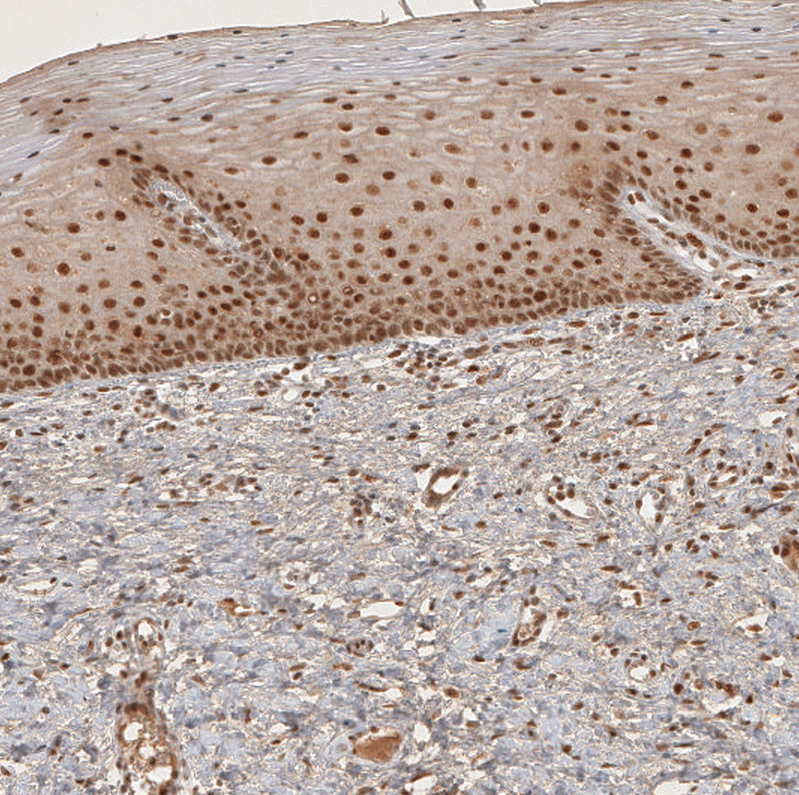

Immunohistochemical staining of human testis shows moderate to strong nuclear positivity in squamous epithelial cells.